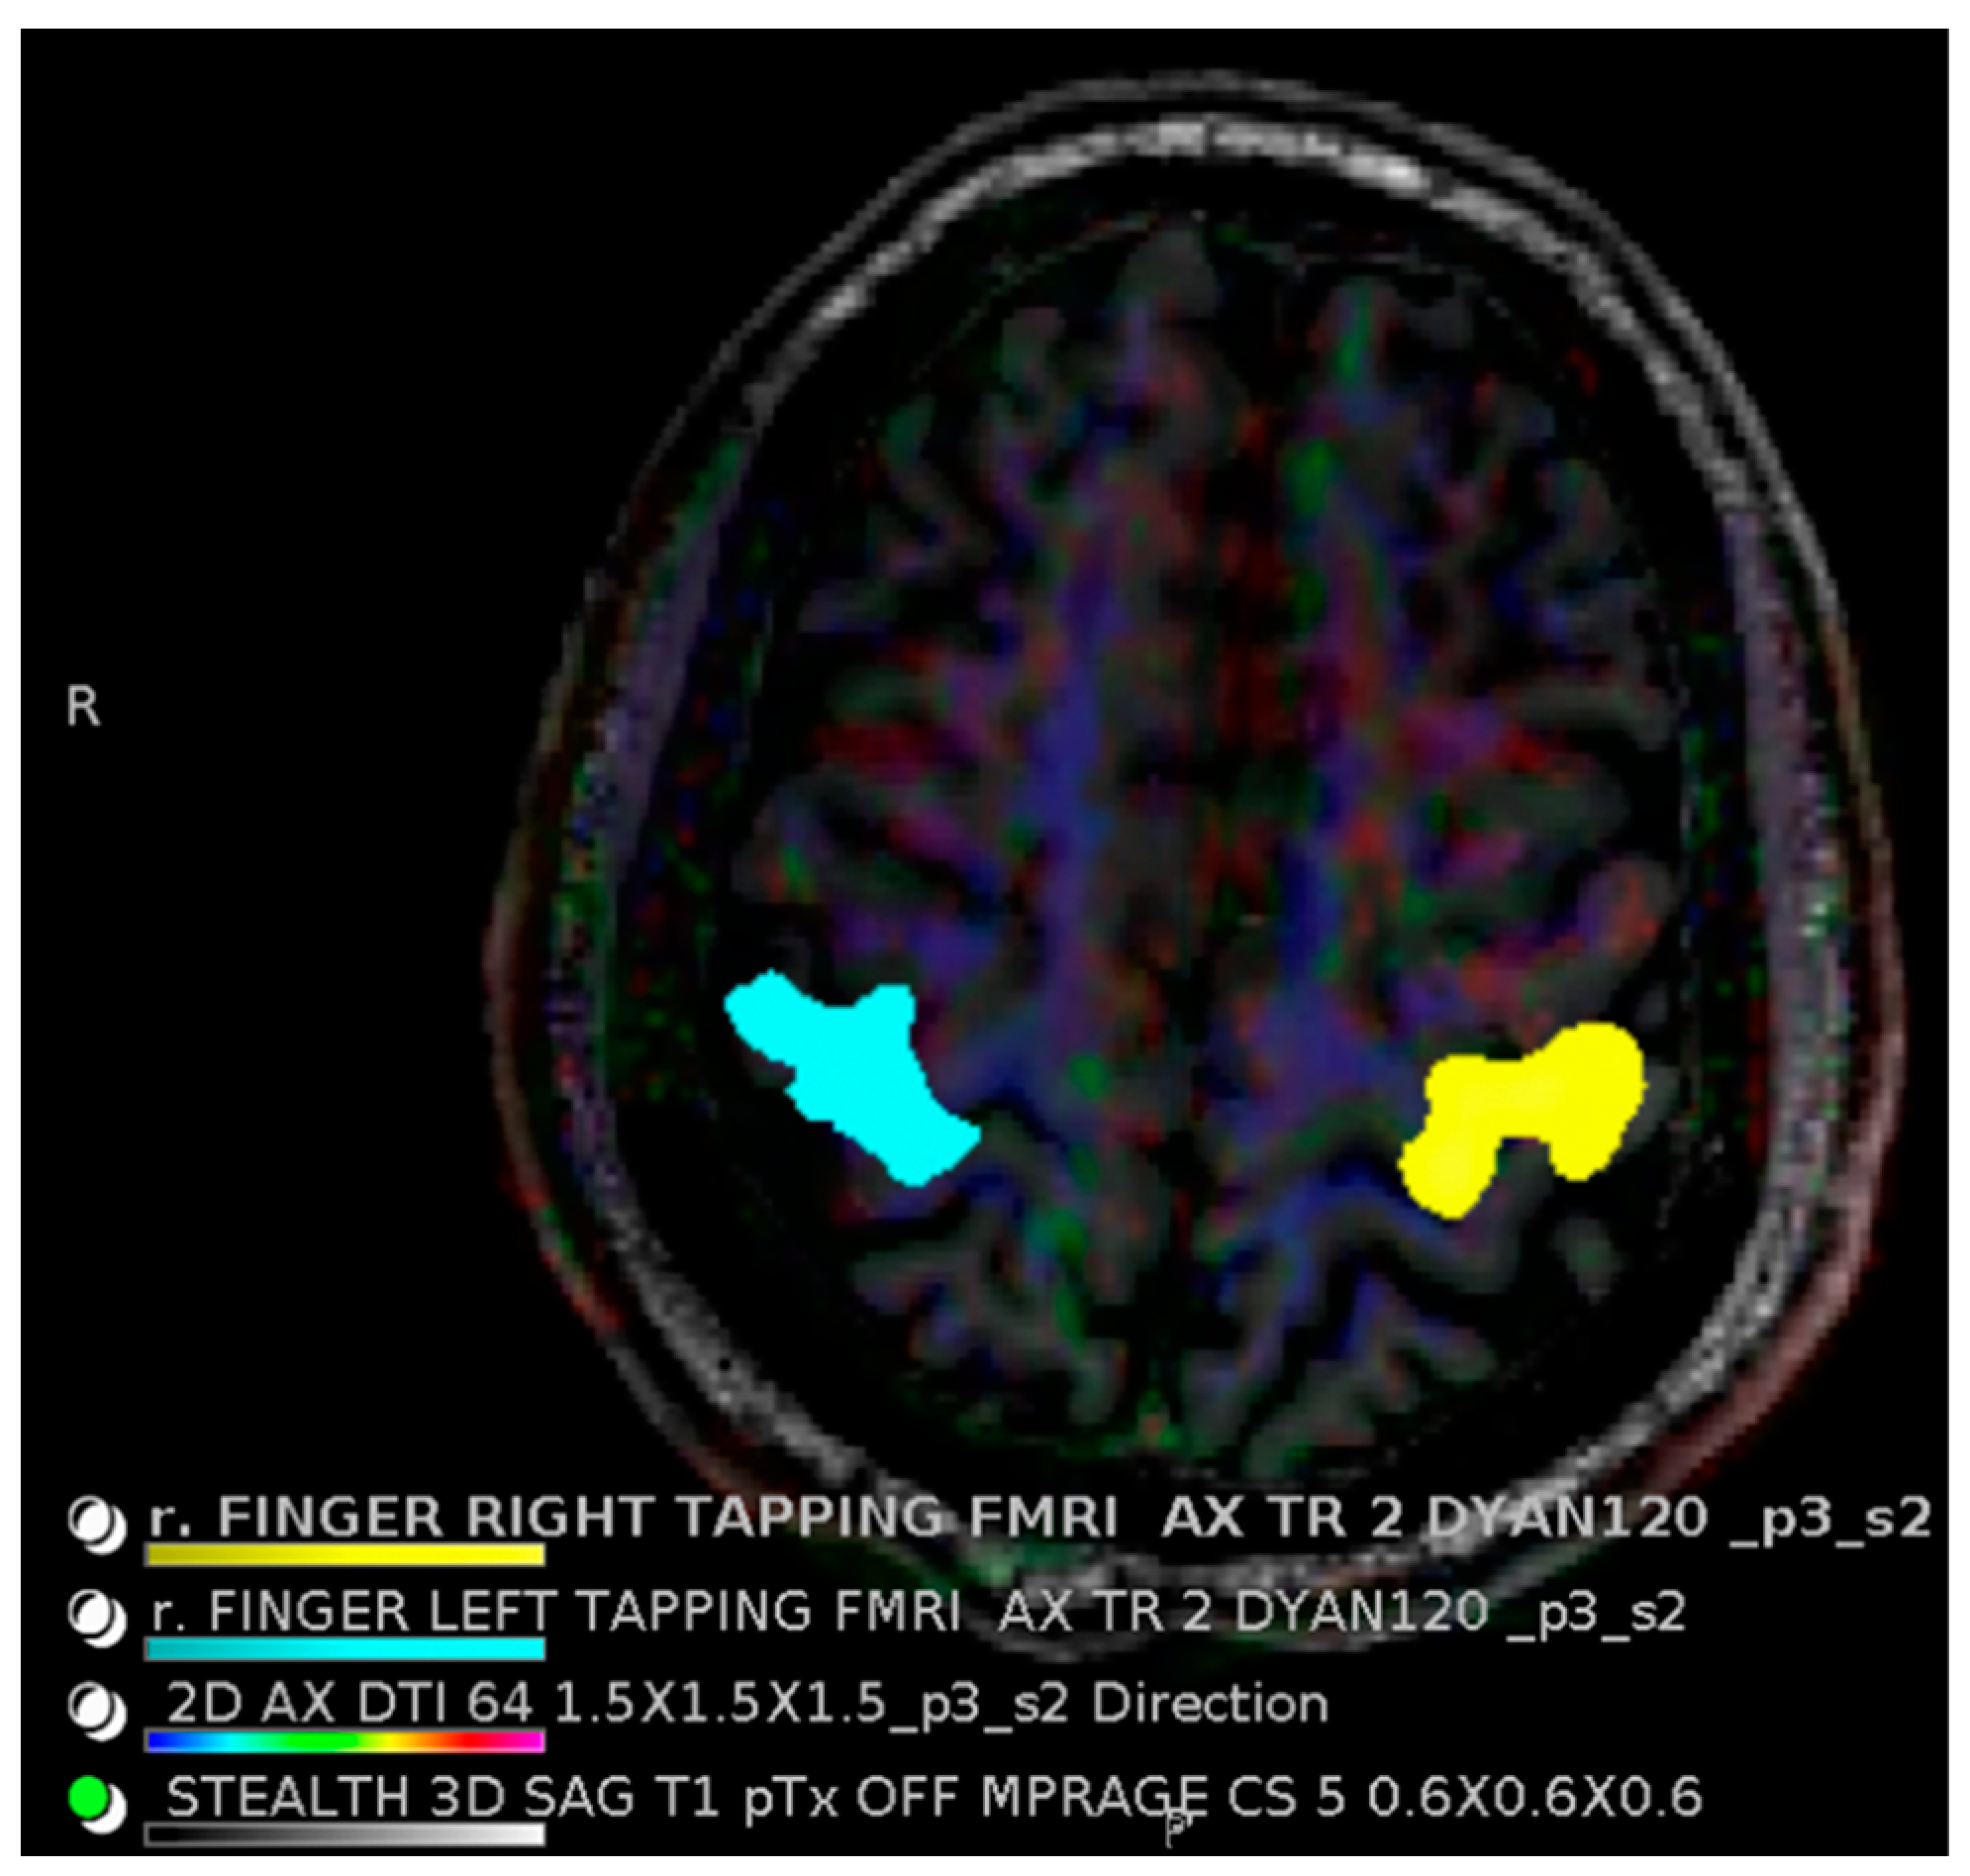

- Vysotski, S.; Madura, C.; Swan, B.; Holdsworth, R.; Lin, Y.; Del Rio, A.M.; Wood, J.; Kundu, B.; Penwarden, A.; Voss, J.; et al. Preoperative FMRI associated with decreased mortality and morbidity in brain tumor patients. Interdiscip. Neurosurg. 2018, 13, 40–45. [Google Scholar] [CrossRef] [PubMed]

- Yacoub, E.; Shmuel, A.; Pfeuffer, J.; Van De Moortele, P.; Adriany, G.; Andersen, P.; Vaughan, J.T.; Merkle, H.; Ugurbil, K.; Hu, X. Imaging brain function in humans at 7 Tesla. Magn. Reson. Med. 2001, 45, 588–594. [Google Scholar] [CrossRef] [PubMed]

- Kreitz, S.; Mennecke, A.; Konerth, L.; Rösch, J.; Nagel, A.M.; Laun, F.B.; Uder, M.; Dörfler, A.; Hess, A. 3T vs. 7T fMRI: Capturing early human memory consolidation after motor task utilizing the observed higher functional specificity of 7T. Front. Neurosci. 2023, 17, 1215400. [Google Scholar] [CrossRef]

- Khanna, N.; Altmeyer, W.; Zhuo, J.; Steven, A. Functional Neuroimaging: Fundamental Principles and Clinical Applications. Neuroradiol. J. 2015, 28, 87–96. [Google Scholar] [CrossRef]

- Agarwal, S.; Welker, K.M.; Black, D.F.; Little, J.T.; DeLone, D.R.; Messina, S.A.; Passe, T.J.; Bettegowda, C.; Pillai, J.J. Detection and Mitigation of Neurovascular Uncoupling in Brain Gliomas. Cancers 2023, 15, 4473. [Google Scholar] [CrossRef]